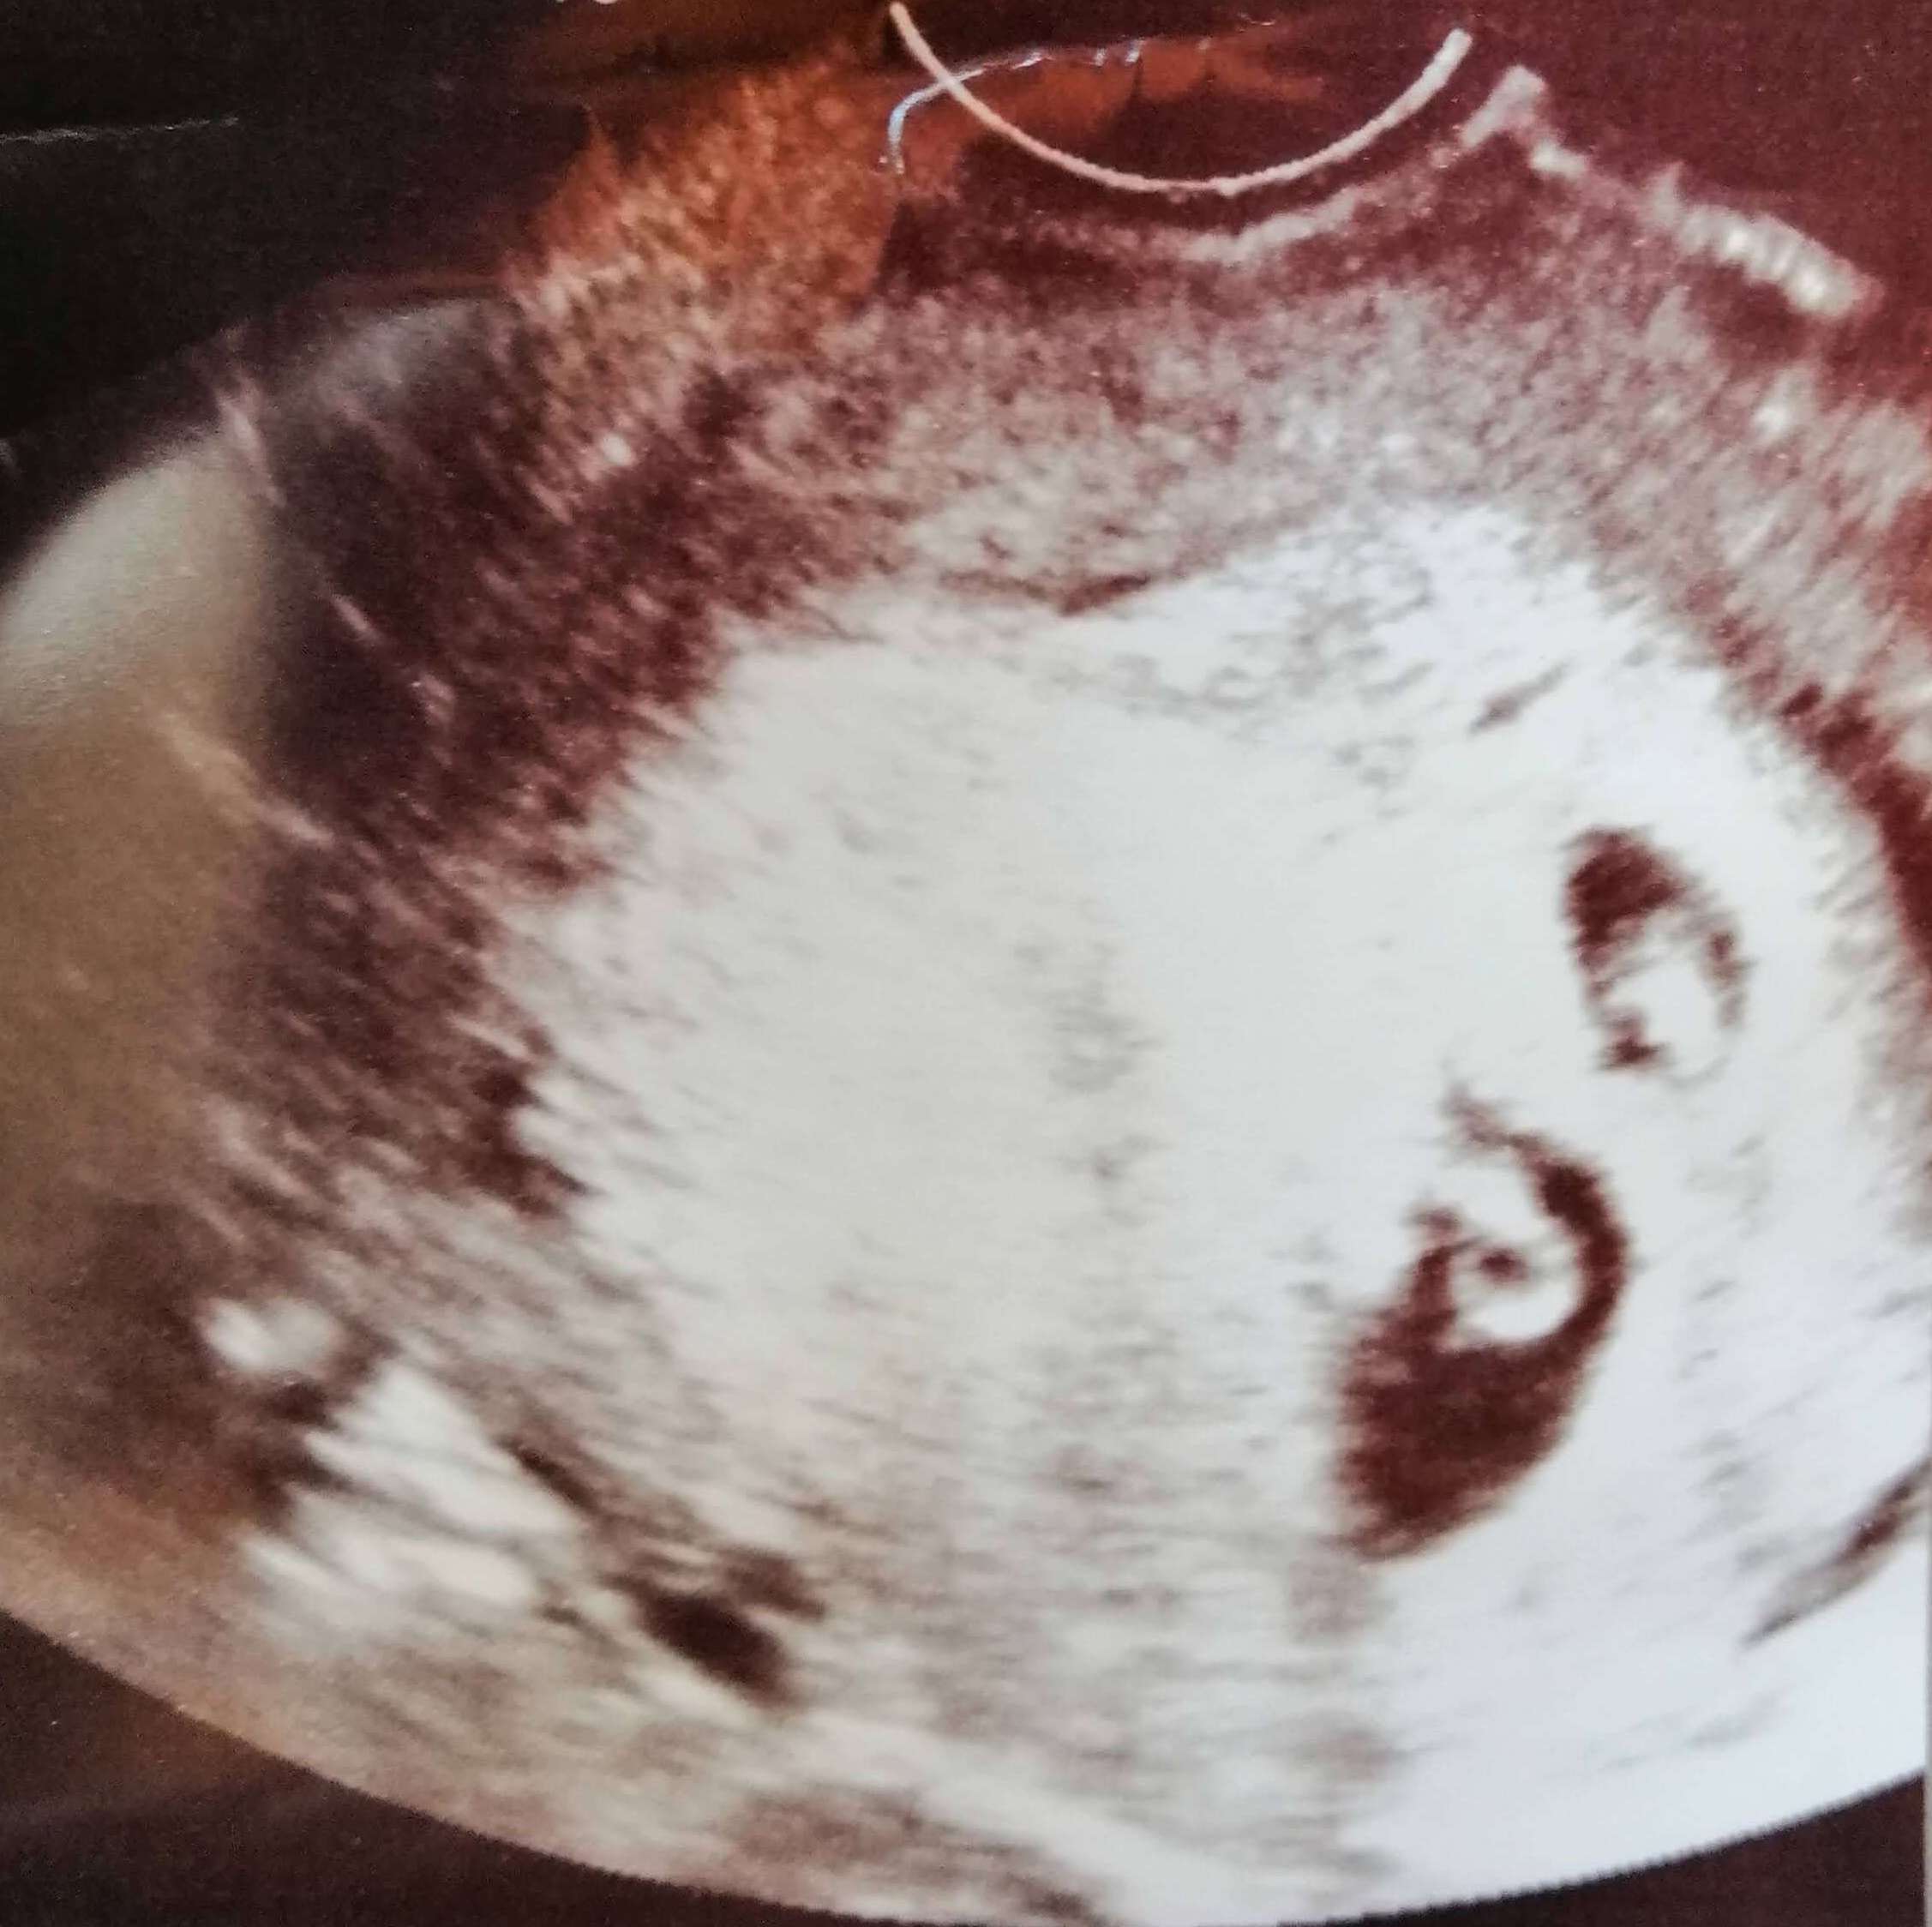

双子の妊娠が確認された時のエコー写真です。

| 双子① | 双子② | |

| 頭殿長 (CRL) | 3.3mm | 3.3mm |

まだまだ不安定な段階での妊娠確認だったので、妊娠確定判断はこの1週間後にしてもらうことになりました。